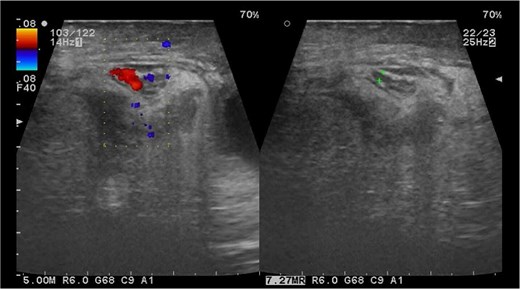

We opted not to begin with a laparoscopic exploration due to a high risk of abdominal contamination, and since the initial procedure was an open hernioplasty, an exploratory laparotomy was instead performed, which confirmed that the appendix was swollen, necrotic, and perforated at its tip, with the release of pus, along with a thrombosed artery (grade IV appendicitis) (Fig. 2). The surgery involved the Pouchet technique for the appendectomy plus invagination of the proximal stump. A Penrose drain was placed in the inferolateral region of the affected scrotum to control any remaining pus and localized swelling. The patient went through the post-surgery period without any issues and was monitored for 5 days to ensure a complete antibiotic course. A right scrotal ultrasound examination revealed no evidence of testicular involvement, and the patient was discharged from the hospital.

Appendectomy grade IV; perforation data, comparison with No. 3 scalpel.